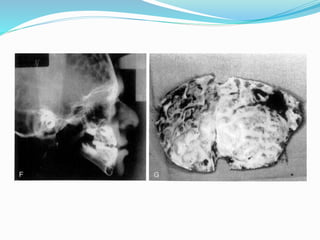

Lefort 3 Osteotomy

Subcranial Lefort 3 Osteotomy

Modified (subtotal)Lefort 3 Osteotomy

Indications

 Osteotomy

 Nose.orbits.zygomas.maxilla

Midface Deficiency

 Frontal bossing

 Petosis

 Dystopy lateral canthal

 Exorbitism-exotropia

 Maxillary hypopalsia

 Maybe hypertelorism

 Tarnsverse deficiency

 C3 malloclusion

 Apertognathia